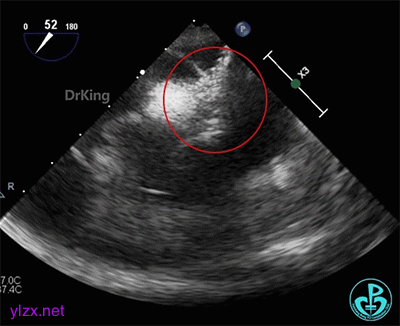

术前经食道超声描述:室间隔连续完整,房间隔中部菲薄,呈瘤样凸向右房面,基底宽约12mm,膨出约8mm。卵圆窝处薄弱,呈纤细线样回声,原发隔与继发隔间见纤细裂隙,入口约0.4mm,出口约0.8mm,卵圆瓣长约20.1mm,原发隔摆动幅度约13mm,继发隔厚约4.5mm,瓦式呼吸后,入口较宽约3.8mm,出口较宽约2.0mm,卵圆瓣左房侧末端迂曲。CDFI裂隙处可见微量左向右过隔血流信号。左心耳显示清楚,内未见异常回声。主动脉内中膜欠光滑,窦部宽约25mm,管腔未见明显狭窄与扩张,CDFI未见明显异常血流信号。各房室腔比例尚可,未见明显节段性室壁运动异常,各瓣膜形态、结构正常,启闭尚可。

超声诊断:先天性心脏病,卵圆孔未闭(长隧道型)。

右心声学造影检查:微泡造影剂经右肘正中静脉、上腔静脉进入右房,充盈良好,可见小楔形负性充盈区,患者瓦氏呼吸后见细小微气泡自裂隙处进入左房,约25~30个,一个裂隙位于卵圆孔入口处,一个位于卵圆孔出口处。